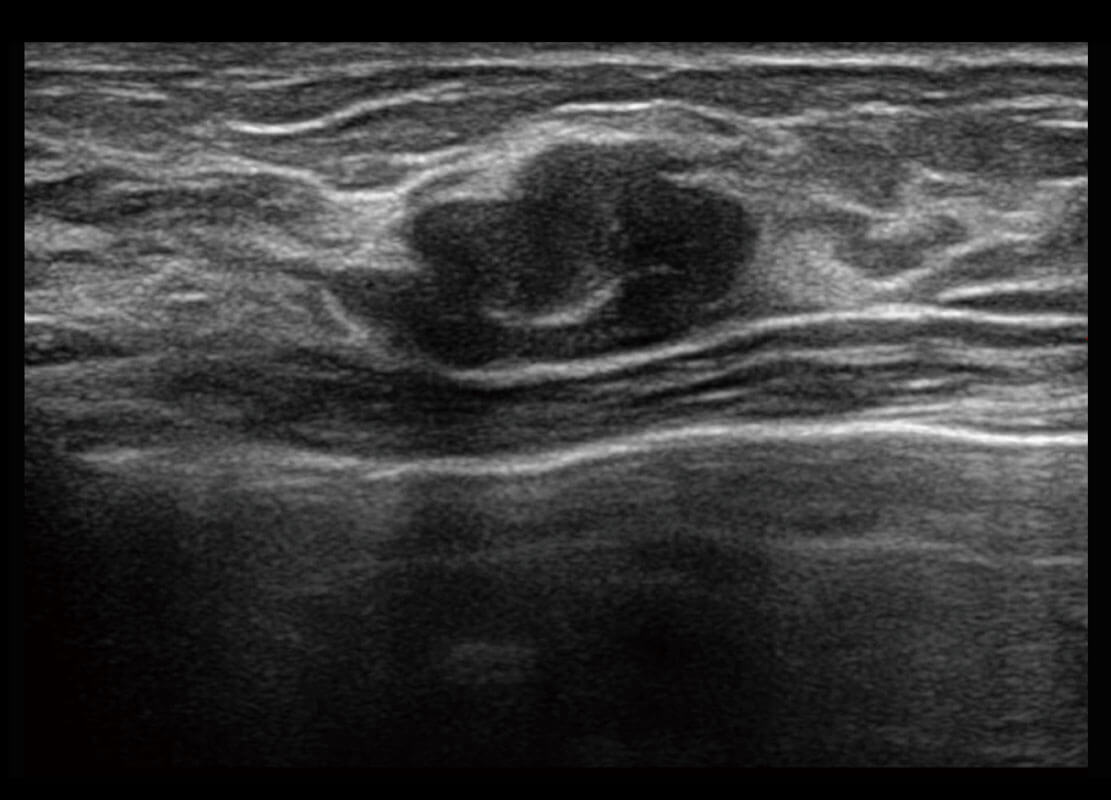

P60优异的图像质量搭载专科探头,在妇科基础疾病的诊断、卵泡生长的监测、输卵管通畅情况的判别等方面为您提供生殖应用方案。

腔内妇科-宫腔分离

腔内妇科-卵巢